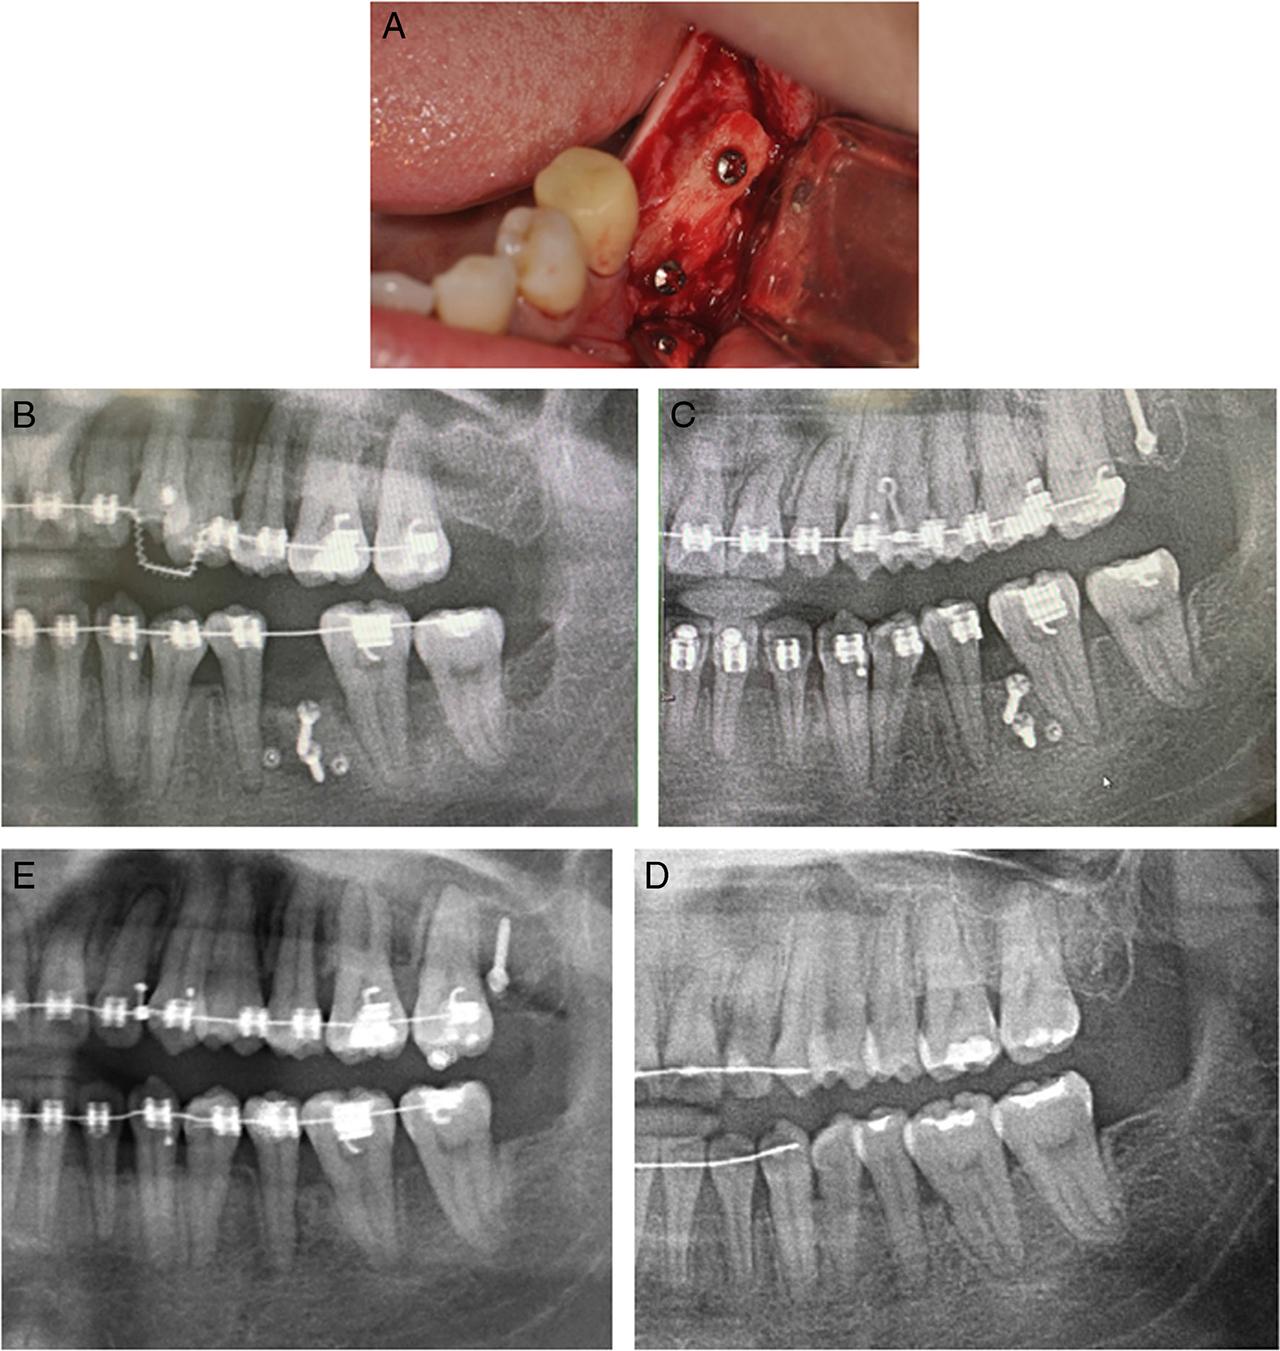

Eleven months after the start of orthodontic treatment, the lower right mandibular edentulous ridge was expanded via periodontally accelerated osteogenic orthodontics (PAOO) and freeze-dried bone allografts (FDBA) grafted to remove the alveolar ridge barrier and enable space closure. An immediate orthodontic force was applied to the teeth. The mandibular right molar was uprighted using an omega loop incorporating a tip-back bend and an uprighting spring (Fig. 2).

Figure 2

In Case 1, PAOO was performed 1 year after the start of orthodontic treatment. (A) Intraoperative photos. The surgical cuts created vertical grooves and a circular corticotomy was performed with high speed piezoelectric tools to join the vertical cuts. Selective medullary penetration was performed to enhance bleeding. Later, freeze-dried bone allografts were placed in the areas that had undergone corticotomy to increase alveolar bone thickness. (B) After the PAOO. (C) One year and 10 months after PAOO.

Rather than a traditional corticotomy, the presented cases used piezoelectric tools for decortication because this approach is minimally invasive, more comfortable for the patient and therefore has greater acceptance.12,13 In Case 1, the PAOO procedure was adopted along with a FDBA allograft. Immediate orthodontic force for molar uprighting was applied without adverse consequences. The root movement was slow but continuous, taking 22 months for the molar root to move through the grafted ridge. In Case 2, a corticotomy was adopted along with an autogenous bone block via a xenograft and guided bone regeneration (GBR). The application of a protraction force was delayed for one month to avoid interfering with the resorbable collagen membrane and tenting screw stability. The space was closed smoothly at a rate of approximately 1 mm per month (Fig. 5B–E). The differences can be attributed to the patient's age, variation in the individual bone remodelling rate, and different graft materials.14,15 An autogenous bone graft, although associated with increased patient morbidity, possessed the ability to initiate osteogenesis and prompt bone remodelling, which might explain the space management efficiency in Case 2 after grafting.15 In Case 1, the mechanics of molar movement also involved root translation into the grafted area. Without A-P movement of the crown, the uprighting induced premature occlusal contact of the molar, which further impeded root movement.